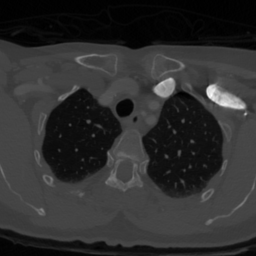

These typical loss functions define the loss of each pixel only on its true and predicted values, but not considering those of other pixels, and aggregate them by weighted averaging or summing without considering the spatial relations between the predictions. Since this type of definition is of local nature, these loss functions may not sufficiently impose a network to learn the shape of an object or the geometry between multiple objects, especially when the amount of training data is small. On the other hand, the ability of the network to learn the shape may be important for better segmenting the objects in medical images since these objects typically have an expected shape or a geometry due to their intrinsic characteristics. One example is the formation of the aortic arch and great vessels in a human body. The aorta and the large arteries and veins (also known as great vessels) are not randomly distributed over the human body. Instead, they are found in a particular geometry due to the human anatomy (Figure 1). Besides, they mostly seem as round objects on a 2D axial image since blood vessels are tubular in 3D. This anatomic information is indeed utilized by human annotators to locate these vessels and delineate their boundaries.

The proposed topology-aware loss function was tested on a dataset that contains CT scans of 24 subjects with prediagnosis of pulmonary embolism. The CT scans were acquired using a 128 slice Philips Ingenuity CT scanner with 1.5 mm slice thickness. A 60 ml of non-ionic contrast material (iohexol; generic name Opaxol) was introduced with a 100 ml saline chaser at 5 ml/s. The data collection was conducted in accordance with the tenets of the Declaration of Helsinki and was approved by Koc University Institutional Review Board (Protocol number: 2022.161.IRB1.064). We randomly split the 24 subjects into the training and test sets. The training set contains 2896 images of 16 subjects; 2234 images of 12 subjects were used to learn the network weights by backpropagation and 662 images of 4 subjects were used as validation images for early stopping. The test set comprises 1431 images of 8 subjects; note that the images of none of these subjects were used neither in the training nor for early stopping.